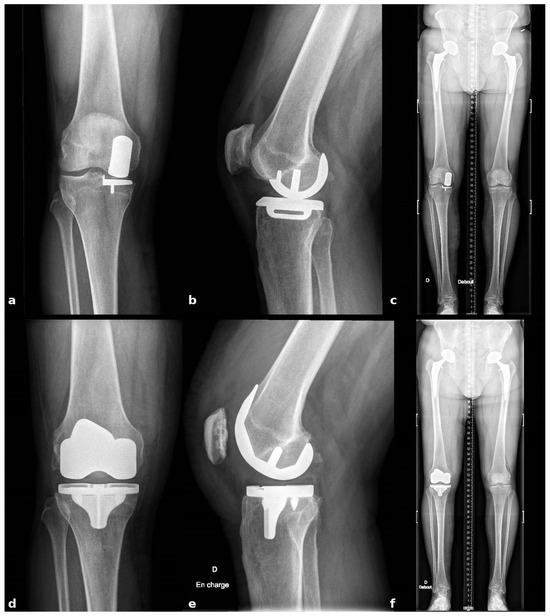

Postoperatively, patients follow a standardized rehabilitation program that encourages immediate mobilization and full weight-bearing. Deep venous thrombosis prophylaxis and early quadriceps activation exercises are initiated on the day of surgery. Postoperative radiographs are obtained to confirm accurate component positioning and restoration of limb alignment (Figure 9).

Figure 9.

Radiographic comparison of preoperative and postoperative component positioning and alignment (a) Preop AP view; (b) Preop Lateral view; (c) Preop Long-leg alignment view; (d) Postop AP view; (e) Postop Lateral view; (f) Postop Long-leg alignment view.

The described workflow enables stable registration despite metallic artifacts from the in situ UKA components and allows bone-sparing implant removal. Functional-alignment planning combined with robotic guidance achieves symmetric extension and flexion gaps without ligament or soft-tissue releases. Localized metaphyseal defects at the former tibial keel site are managed with impacted autologous cancellous graft harvested from femoral resections. Final implant placement matched the preoperative plan, and postoperative radiographs confirmed restoration of limb alignment and appropriate component positioning.